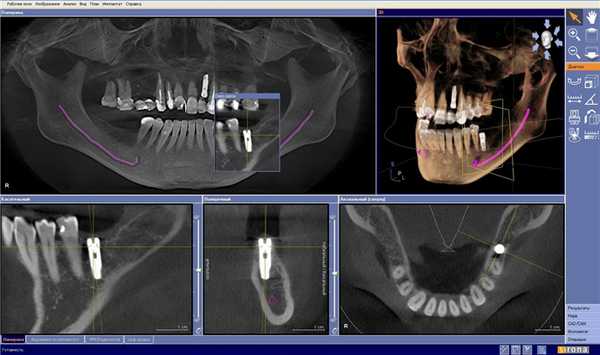

До внедрения 3D КТ зубов в СПб ортопантомография была ведущим методом исследования зубов, челюсти, ротовой полости. Преимущества КТ - это трехмерное моделирование исследуемой области, позволяющее с максимальной точностью исследовать каждый миллиметр ткани на пространственном снимке. Челюстно-лицевые хирурги, стоматологи на 3D-модели оценивают характер патологии, выбирают тактику лечения.

Золотым стандартом стоматологической диагностики считают конусно-лучевые томографы. Оборудование позволяет детально изучить полость рта, но не указывает мелкие детали при сравнении с КТ головы.

Цифровой рентгеновский снимок - плоскостное изображение. Трехмерная компьютерная томограмма - модель зубочелюстной системы, помогающая прогнозировать ход имплантации, протезирования, грамотно удалить поврежденные зубы. Низкое облучение позволяет применять сканирование у детей, подростков для обнаружения непрорезавшихся зачатков, выявления аномалий.

КТ сканирование всей ротовой полости - как проходит

Послойная визуализация объекта обеспечивается за счет рентгеновских срезов, которые оборудование делает через заданное количество миллиметров. Мультиспиральные томографы (МСКТ) оснащены несколькими головками, выполняют сканирование быстрее даже при шаге 1 мм. Томограммы характеризуются высоким разрешением, позволяющим обнаружить мельчайшие воспалительные полости (кисты, абсцессы).

Нативное КТ сканирование всей полости рта безболезненно, неинвазивно. Длительность исследования не превышает 10 минут. Сканы обрабатываются программным приложением с формированием 3D-модели. Трехмерный цифровой снимок челюсти позволяет во всех ракурсах рассмотреть зубочелюстную систему.

Рентгеновское исследование на конусно-лучевом томографе выполняется стоя. Подходит для пациентов с фобиями замкнутых помещений. При сравнении с КТ-обследованием не позволяет получить истинные размеры. Рентгеновская ортопантомография сопровождается большей лучевой нагрузкой, поэтому постепенно утрачивает диагностические позиции.

Дентальная компьютерная томография - что показывает

Применение компьютерной томографии челюсти помогает стоматологам и челюстно-лицевым хирургам диагностировать:

Обследование используется при планировании имплантации, протезирования, операций по удалению опухоли. Составление грамотного плана лечения без КТ-сканирования невозможно.

Полную информацию о состоянии верхней или нижней челюсти получают с томографией в 3-ех проекциях - поперечная (аксиальная), вертикальная (сагиттальная), фронтальная.

Экстренную дентальную диагностику рационально проводить на мультиспиральном компьютерном томографе (МСКТ) с целью изучения кровоснабжения черепа, мозга, выявления воспаления околоносовых полостей. Процедура используется перед планированием сложных реконструктивных операций.

Пространственное ремоделирование помогает имплантологу правильно определить тип имплантата, форму протеза для оптимального приживления.

Преимущества компьютерного сканирования рта

Тонкосрезовое КТ пазух носа, челюсти вытесняет рентгеновские методы не только из-за снижения лучевого облучения. Если использовать компьютерную томографию, удается визуализировать не только кости, но и мягкотканый компонент, воспалительные очаги. Четкость снимка помогает изучить самые тонкие детали, обнаружить мелкие трещины зубов, пародонта. Изучение во многих плоскостях 3D-модели с масштабированием один к одному показывает истинные размеры объекта.

В заключение укажем, что при планировании имплантации сложно обойтись без КТ-срезов с трехмерной картиной, необходимой для точных замеров. Метод практикуется отоларингологами, челюстно-лицевыми хирургами, стоматологами.